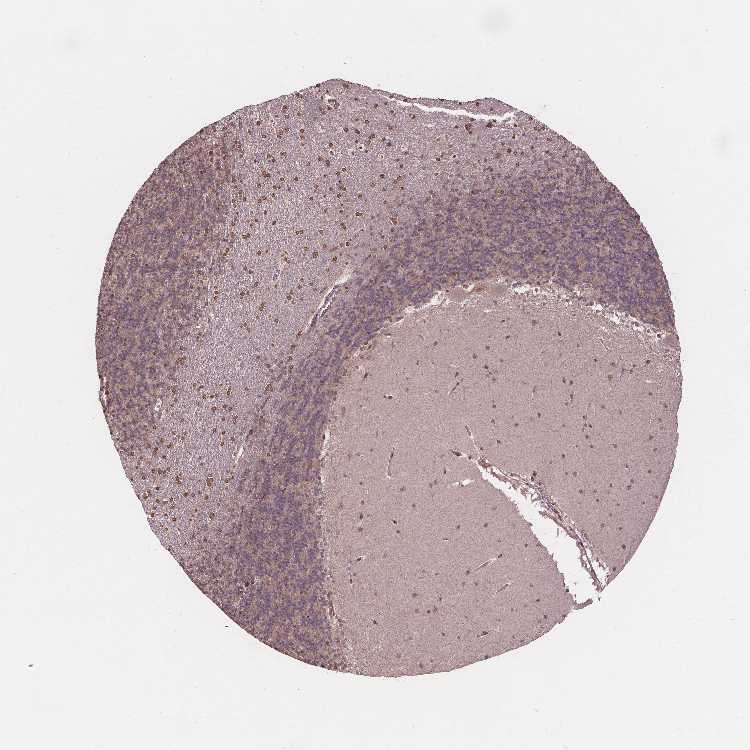

BRAIN CEREBELLUM Show tissue menu

CEREBELLUM - Expression summary

Cells in granular layer: Low

Cells in molecular layer: Medium

Purkinje cells: Medium

CEREBELLUM - Antibody stainingi

Antibody staining in the annotated cell types in the current human tissue is reported as not detected, low, medium, or high, based on conventional immunohistochemistry profiling in selected tissues. This score is based on the combination of the staining intensity and fraction of stained cells.

Each image is clickable and will lead to virtual microscopy that enables deeper exploration of all samples and also displays staining intensity scores, fraction scores and subcellular localization as well as patient and tissue information for each sample.

Antibody HPA065302Antibody CAB069903

Purkinje cells HighLow

Cells in granular layer Not detectedLow

Cells in molecular layer LowMedium